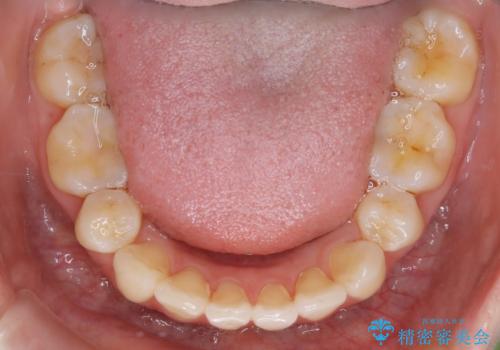

【再矯正】後戻りによるガタつきをマウスピースで改善!

- 以前、中学生から高校生にかけてワイヤー装置による抜歯矯正を経験されている患者さんで、大人になってからのライフスタイルの変化でリテーナーを継続使用することができず、ガタつきが目立つようになってきてしまったのでもう一度矯正治療がしたいという主訴でご来院されました。

既に上下左右の4番目の歯が抜歯されているため、今回の治療では抜歯をせず歯の移動だけでガタつきを治す必要があり難易度が高くなっていました。